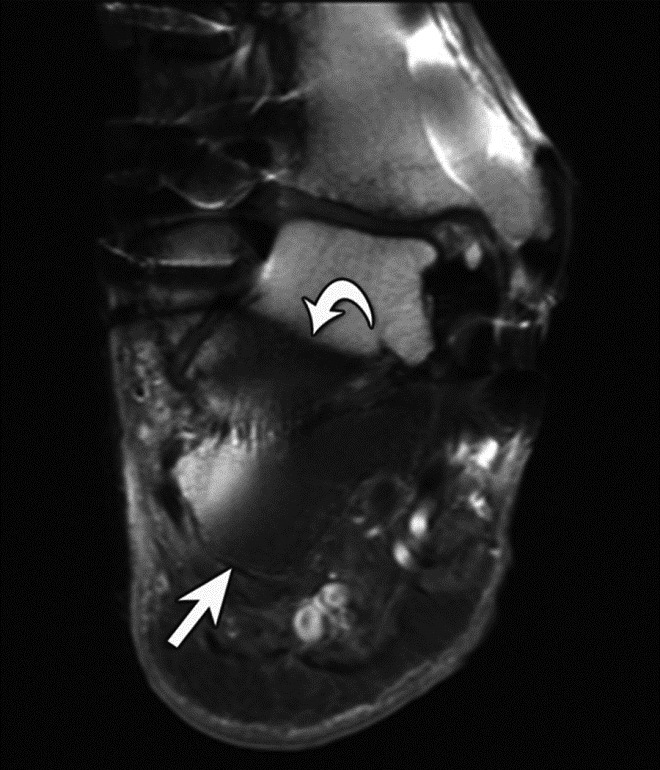

Inversion Recovery Imaging. (A) Axial spectral adiabatic inversion recovery (SPAIR) image used during MR examination of the abdomen and pelvis demonstrates large regions of susceptibility due to bilateral metal-on-metal hip arthroplasties as this technique is highly sensitive to field inhomogeneities.

| Inversion Recovery Imaging. (B) Axial STIR MR image in the same patient reveals fluid-signal pseudotumor (arrow) adjacent to the left greater trochanter, which was obscured on prior examination. |

On MRI, pseudotumors will appear as solid, cystic or mixed masses adjacent to and possibly communicating with the hip joint with potential intralesional or peripheral low T2 signal, reflecting metal deposition (Figure 24) (Chen, 2011). Solid lesions more commonly occur anteriorly, usually within the psoas muscle and may extend proximally into the pelvis (Figure 25) (Ostlere, 2011). Predominantly cystic lesions typically arise from the posterior joint space and may or may not demonstrate wall-thickening. Lateral lesions usually involve the trochanteric bursa and often communicate with the joint space. Differentiation of cystic and solid lesions may be difficult and the use of post-contrast imaging is not helpful for lesion detection, particularly due to surrounding metallic artifact. There may be involvement of the adjacent osseous structures with associated erosions, as well as the soft tissues, particularly the gluteal tendon attachments with resulting tendon disruption and muscle atrophy (Figure 26) (Anderson, 2011). In rare cases, the reactive process may involve pelvic or lower extremity arteries or the femoral nerve, particularly when occurring anteriorly (Clayton, 2008; Chen, 2011). At present, there is no established pathway for the management of metal-on-metal pseudotumor patients, and follow-up imaging may be performed to assess lesion progression before proceeding to revision, especially with small lesions or minor symptoms.